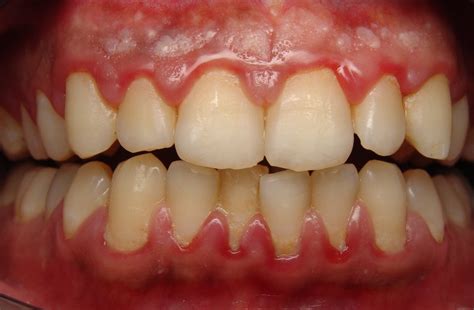

When gingivitis develops, these characteristics change noticeably. The most obvious visual sign is a change in color—gums affected by gingivitis often appear red or dark red, sometimes even purplish in severe cases. This redness is caused by increased blood flow to the inflamed tissue. The gums may also look shiny or glossy rather than having their normal matte appearance, and they lose their firm texture, becoming soft and puffy instead.

In advanced gingivitis, the visual changes are unmistakable. The gums appear bright red or purple, significantly swollen, and may feel spongy to the touch. Bleeding occurs easily and frequently, sometimes even spontaneously. The gum tissue may begin to recede noticeably, exposing more of the tooth surface and potentially the root. At this stage, without intervention, gingivitis is on the verge of progressing to periodontitis, which involves bone loss and is irreversible.